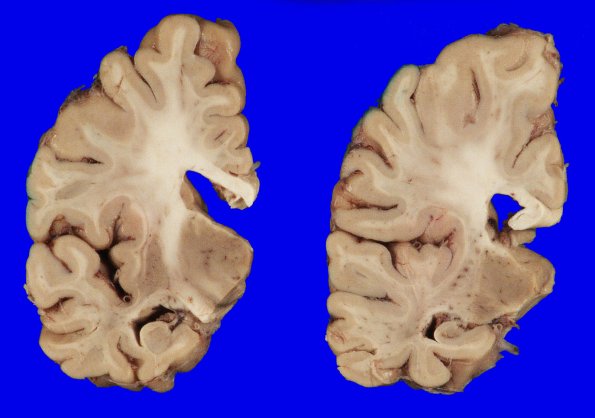

Coronal slicing revealed mild dilatation of the lateral ventricles with rounding of the angles; there was increased space in the inferior horn of the lateral ventricle and the hippocampus was small.